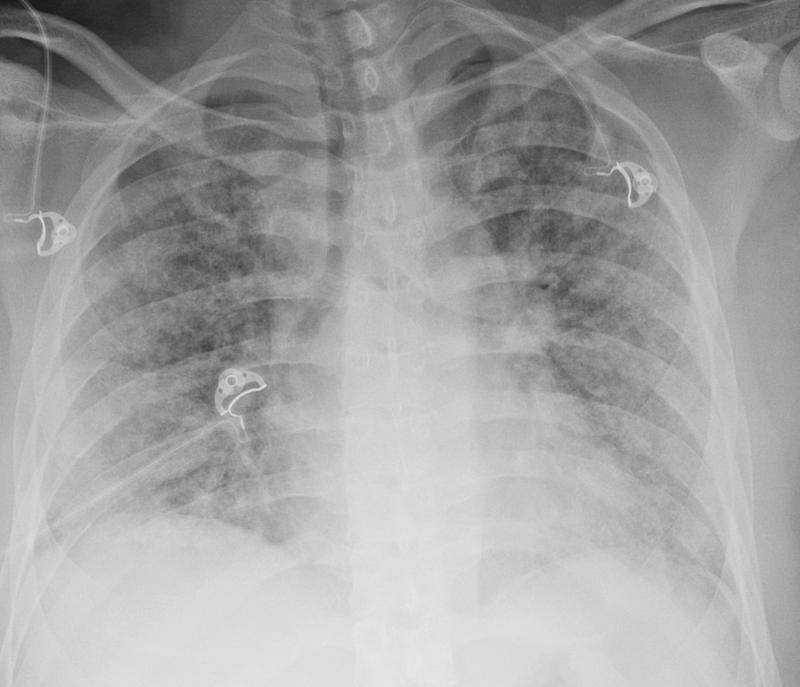

TRALI (transfusion-related acute lung injury)

TRALI (transfusion reaction)